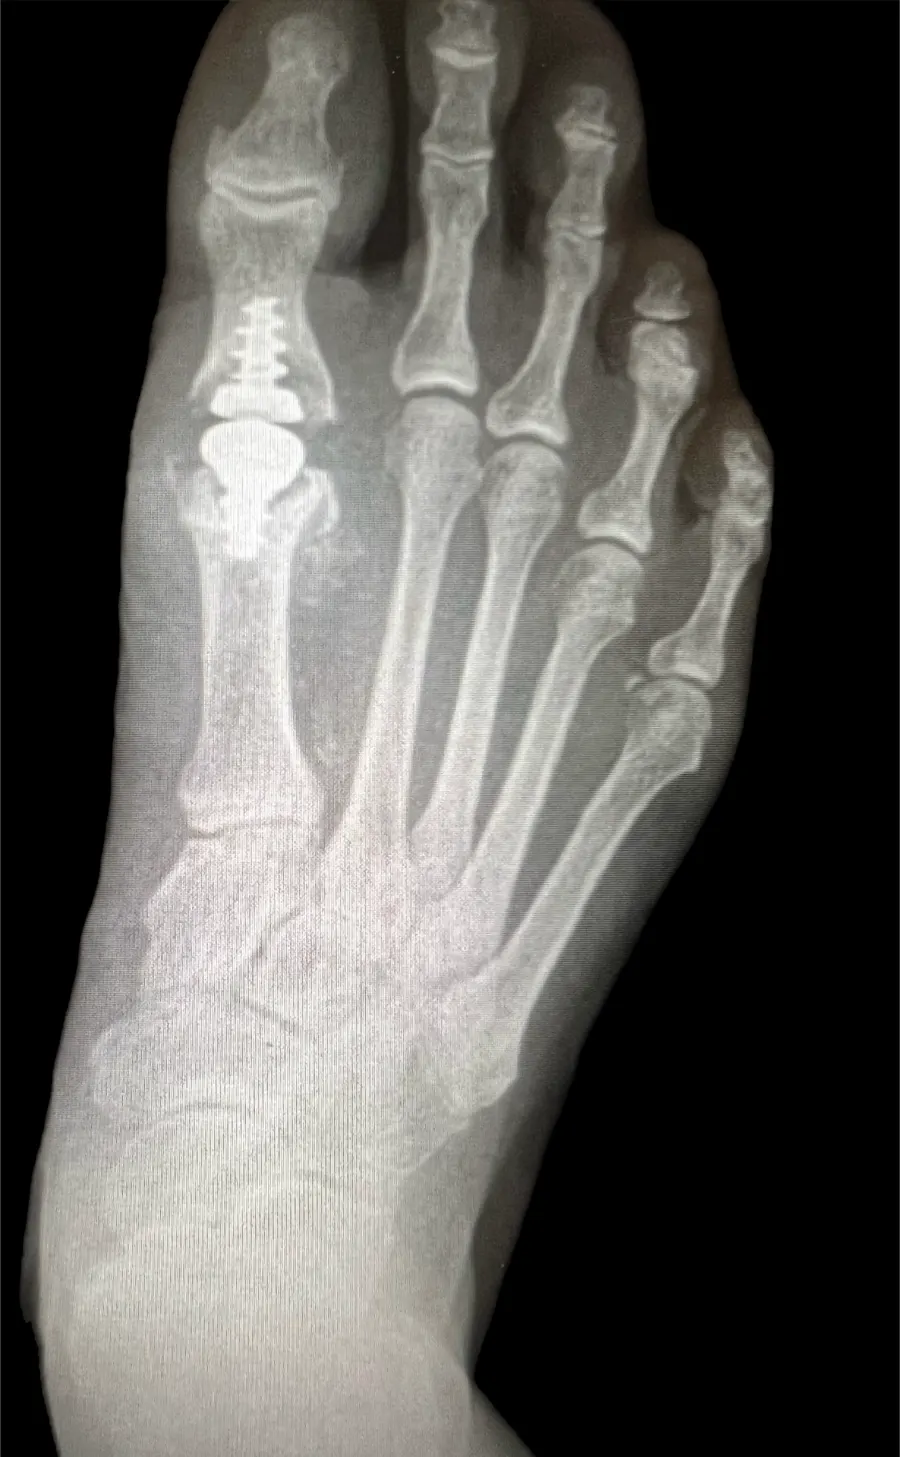

Surgical Intervention at Stepwell Institute is never a “one-size-fits-all” solution. We view surgery as a precise tool used to restore the natural biomechanics of the foot and ankle when non-invasive methods have reached their limit. Our philosophy centers on individualized surgical planning—using advanced imaging to map out the procedure before you ever enter the operating room. From correcting bunions and hammertoes to performing ligament repairs and fracture fixations, Dr. Yakov utilizes techniques designed to minimize trauma to the surrounding tissues, thereby reducing the risk of complications and ensuring a more stable, long-term result for our patients.

Our Case Study